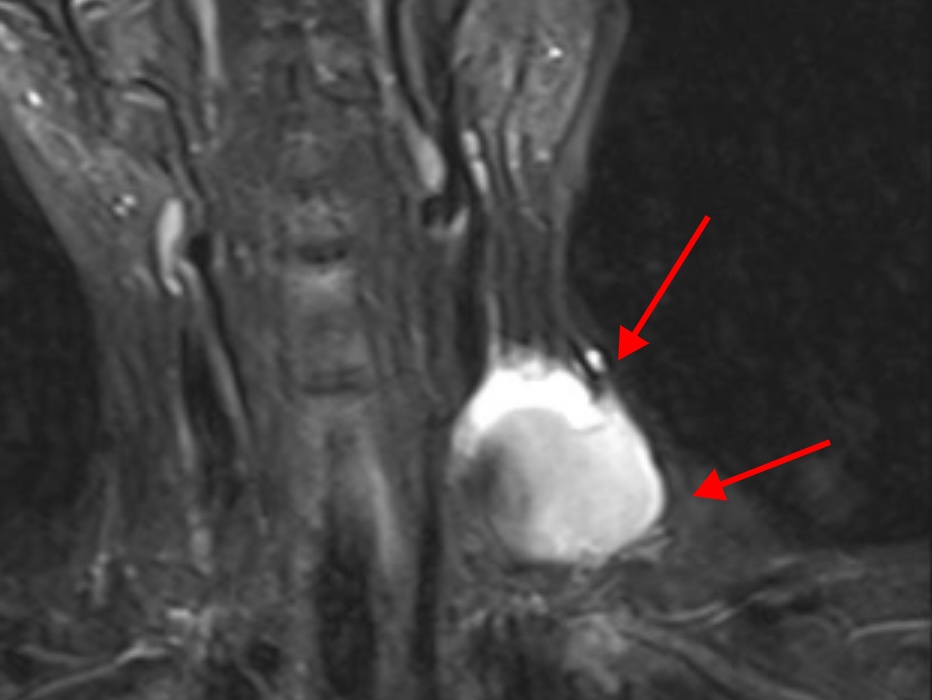

冯医生仔细询问文女士的病史,对病变部位进行了详细的专科查体,结合文女士既往的检查资料与影像图片,冯医生当即明确左颈内静脉假性动脉瘤的诊断,并且该疾病的发生与文女士症状出现当天的颈部按摩可能存在直接的关系。

冯医生表示,文女士的静脉瘤体巨大,最大直径有7cm,一旦破裂会有生命危险;同时,静脉瘤体中有大量血栓,瘤体破口长度约2cm,存在血栓脱落导致肺栓塞的风险;静脉瘤病史时间较长,局部有血栓性静脉炎表现,内部组织粘黏情况较重,如何精准剥离黏连组织,切除肿块的同时重建颈部静脉是手术的关键,同时注意避免损伤胸导管,造成难治性淋巴漏。

手术过程中,冯医生首先游离左颈内静脉远端正常段并悬吊带悬吊备用,直视下穿刺左颈内静脉并引入6F短鞘,导入10mm球囊对左颈内静脉近心端进行球囊阻断。在病变血管近、远端同时阻断条件下,对颈内静脉瘤进行解剖,打开瘤腔,找到破口后予以缝合,同时清除瘤腔内血栓。